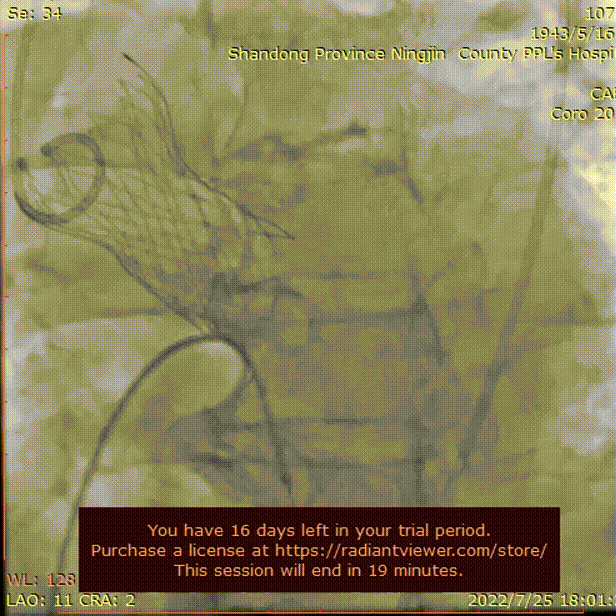

主动脉根部根部造影

直头导丝跨瓣

术者团队用25mm球囊预扩,结合瓣环及球囊预扩情况,预装AV29型号瓣膜。患者横位心,在抓捕器辅助下输送器过弓。

球囊预扩

造影评估

术者结合DSA影像,多角度观察瓣膜情况,在瓣膜释放至工作位造影。

初始定位释放

工作位

无明显返流,瓣膜形态佳,工作稳定。

工作位评估

完全释放